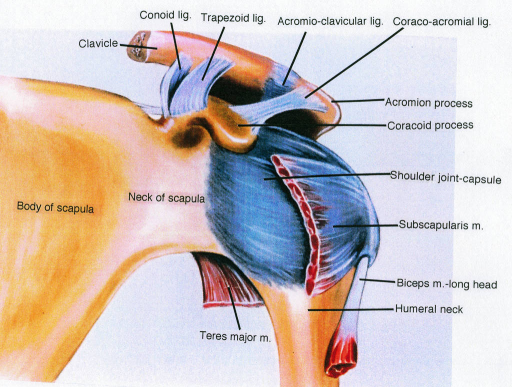

Glenohumeral ligament: анатомия и функции плечевого сустава